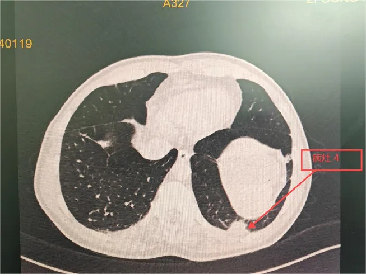

明确诊断后,主管医师予以相应的治疗方案,程大叔的咳嗽、胸痛症状迅速得到了缓解;1月后复查胸部CT,提示肺部阴影较前明显吸收;程大叔悬着的心,终于放下了。

治疗1月后